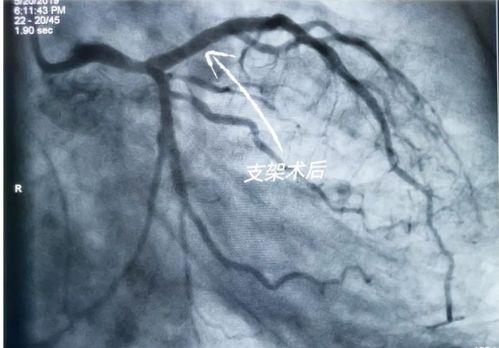

三、国产心脏支架的应用

国产心脏支架在我国的应用非常广泛。据统计,我国每年约有数十万例心脏支架手术,其中大部分采用了国产心脏支架。这些支架在临床应用中表现出良好的效果,为患者带来了福音。